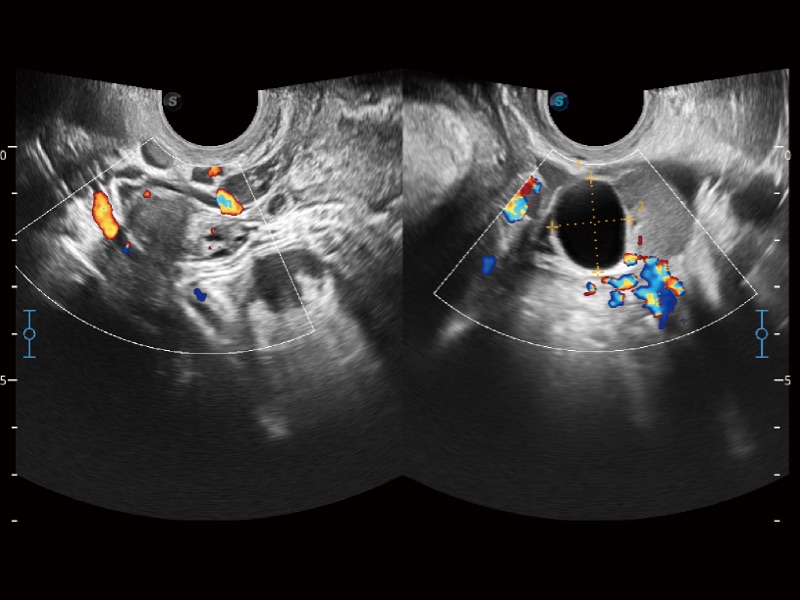

• 妇产科应用